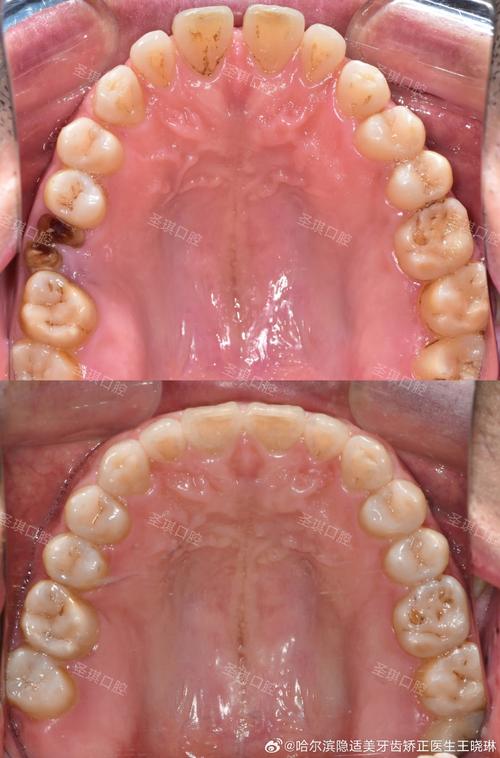

矫治期间,患者需特别注意口腔卫生,使用正畸专用牙刷、牙线、冲牙器等工具清洁牙齿及矫治器,避免龋齿和牙周炎;饮食上避免食用过硬(如坚果、骨头)、过粘(如口香糖、年糕)的食物,防止托槽脱落;若托槽脱落或弓丝刺嘴,需及时联系医师处理;严格按照医嘱复诊,确保治疗效果。